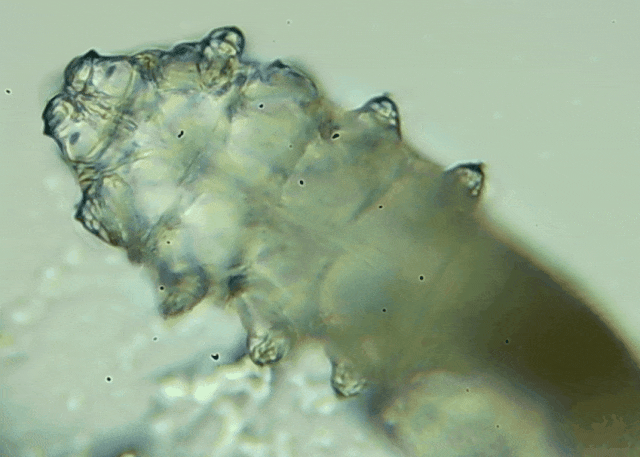

操作:醫(yī)生會(huì)在每只眼睛的上下眼瞼各拔3根典型睫毛,置于光學(xué)顯微鏡下觀察。報(bào)告解讀:任一眼瞼螨蟲數(shù)量≥3 條 →陽性,需要干預(yù)。優(yōu)勢(shì):無創(chuàng)、快速、直觀;當(dāng)場(chǎng)給你看“活的”螨蟲在睫毛上爬,視覺沖擊堪比大片。